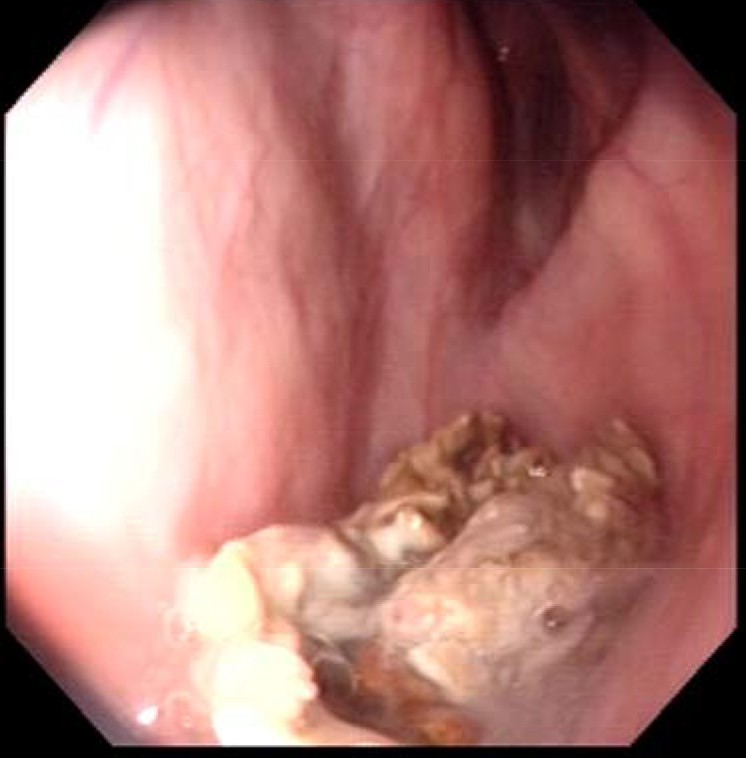

les photos des poches avant le curtage de 10j

Édité par kristine.19 le 21-04-2017 à 09h56